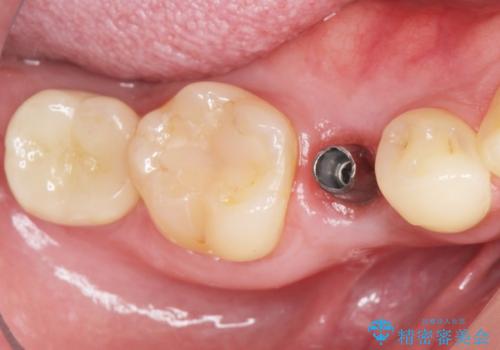

- ¥320,000 (インプラント、既成アバットメント、仮歯、クラウン)費用は治療当時の料金となります

自然な仕上がりと咬み心地に喜んで下さいました。

「低予算でしっかりした治療を受けることができた」とご満足頂けました。

インプラントの種類:アルファタイト

クラウンの種類:オールセラミッククラウン スタンダード